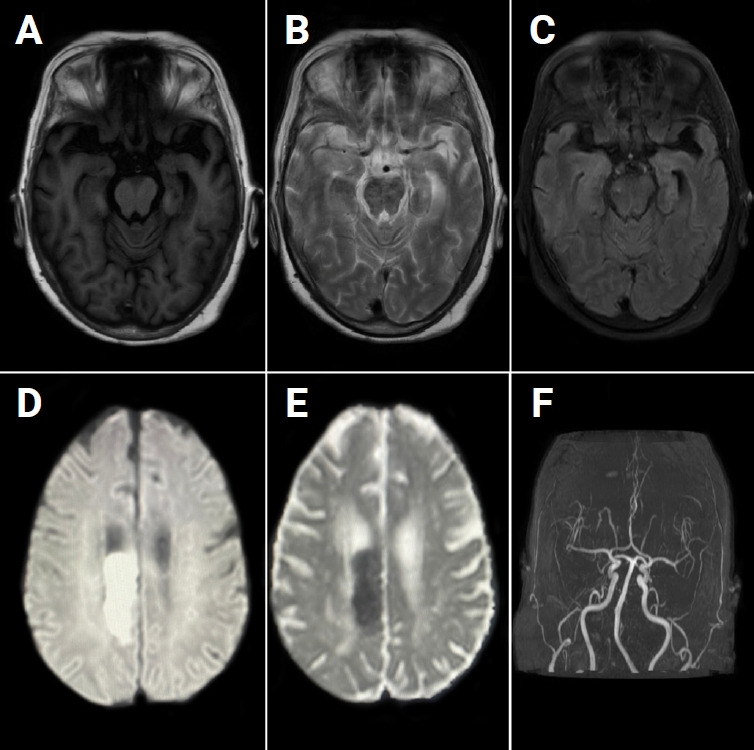

Anti-N-methyl-ᴅ-aspartate (anti-NMDA) receptor encephalitis is a well-known autoimmune encephalitis caused by antibodies against the GluN1 subunit of the anti-NMDA receptor (anti-NMDAR). Stroke, characterized by abrupt focal neurological deficits due to ischemic or hemorrhagic vascular insults, is rarely preceded by anti-NMDAR encephalitis. Here, we described a case of a 69-year-old female without any prior comorbidities who presented with acute stroke and left hemiparesis with a history of recent onset of neuropsychiatric symptoms. Her cerebrospinal fluid was positive for anti-NMDAR antibody, and significant improvement was noticed after the initiation of immunotherapy. In this patient, stroke occurred following anti-NMDAR encephalitis; however, the pathophysiological link between the two remains unclear. This case presents an interesting and rare clinical intersection between stroke and anti-NMDAR encephalitis, highlighting the difficulty of neurological diagnosis. Due to the unusual association of such pathological conditions, this case contributes to the broader understanding of potential connections between stroke and autoimmune encephalitis, emphasizing the need for a multidisciplinary approach to diagnosis and management.